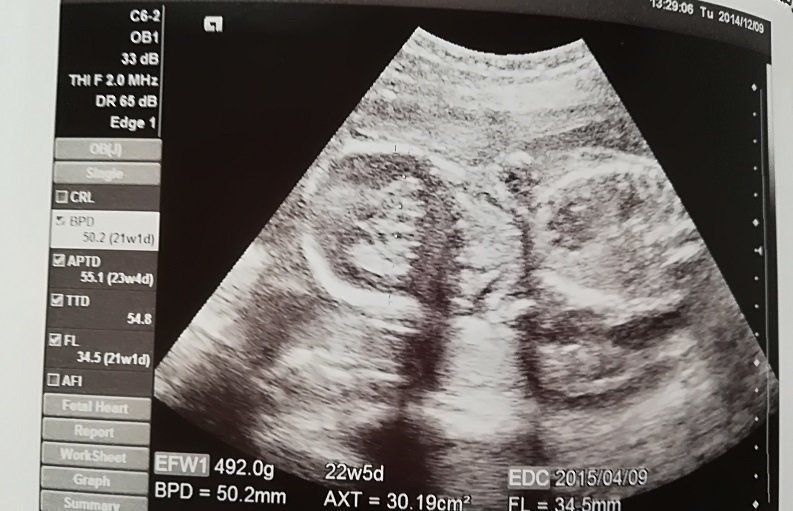

妊娠22週目のエコー写真

骨もくっきり分かります。「なんとなく女の子かも」と医師に告げられました。夫は男子希望だったため、そっけない反応。今から思い出しても腹立たしいです(笑)。おなかが出始めたので、ネット通販でマタニティーガードルや腹巻を買いそろえたのもこの時期。どこまで大きくなるか分からないのが不安でLLサイズにしましたが、正解でした。とにかく食欲がわいて、つわりで食べられなかった分をすぐに取り戻してしまいました。